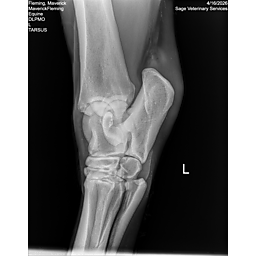

**Maverick sells at the Colorado Horse Sale’s Best of the West Select Sale on May 30th in Castle Rock, CO - He will complete the riding & handling Sift Exam, baseline veterinary exam, and will sell with 4 total radiographs (DLPMO & Front Foot Lateral)**